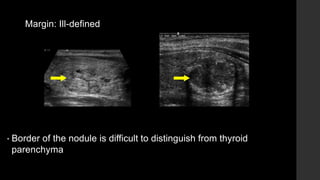

Margin: Ill-defined

• Border of the nodule is difficult to distinguish from thyroid

parenchyma